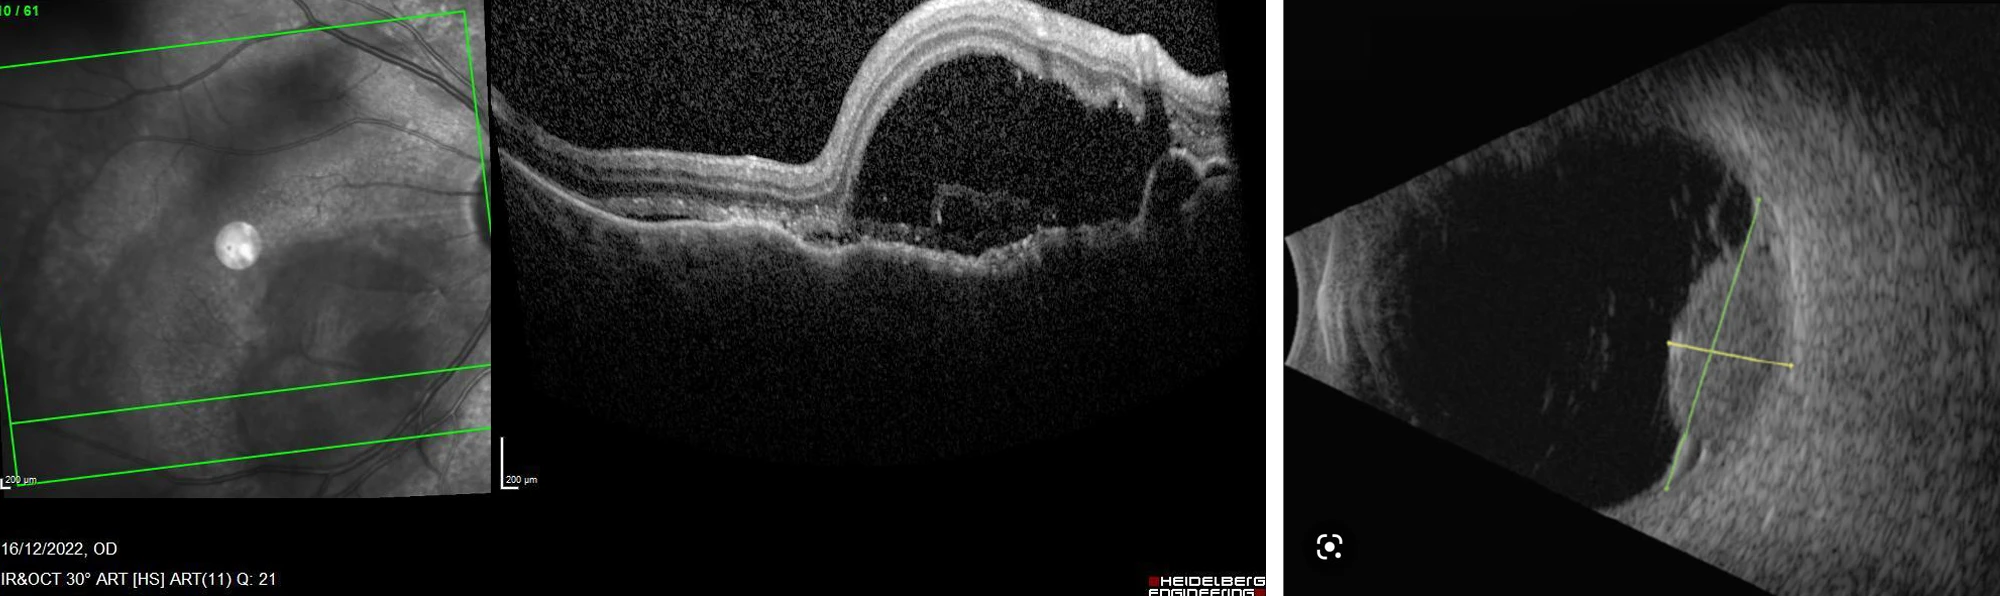

A 64-year-old woman presents with slightly reduced vision in the right eye.

She described “feeling sick” for the last 4 weeks. No significant ocular or medical history was reported.

VA 6/18 OD, 6/6 OS

Answer D

- Mean diameter 9.5mm with thickness of 3.2mm

- Most commonly yellow in colour

- Primary site detected before uveal tumour in 2/3 cases

- Uvea most common site of ocular metastases due to large blood supply

- Choroid (88%), Iris (9%), ciliary body (2%)

- Breast most common site for primary in females

- Lung most common site for primary in males

- Kidney and GI malignancy next (4% each)

- Unknown in approximately 1 in 6